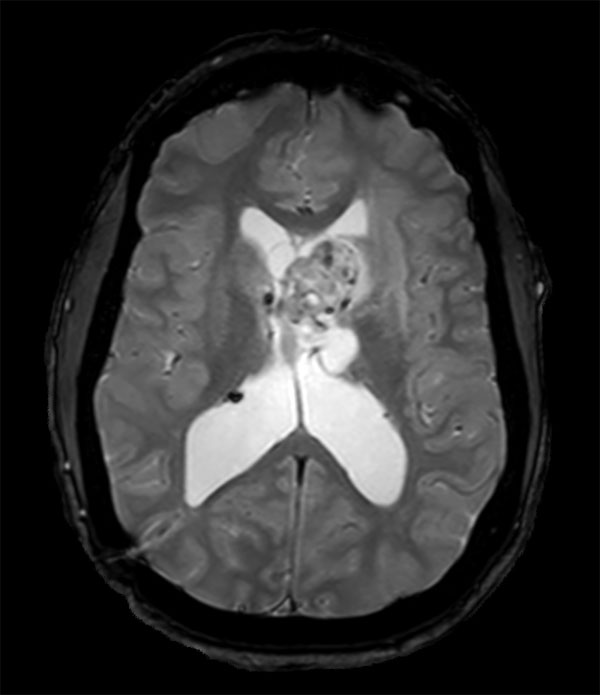

Axial T2w FLAIR